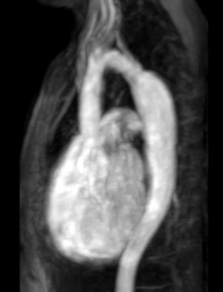

Blood Vessel Problems (Aortopathy and Connective Tissue Disease)

Description: There are many types of disorders that children are born with that can cause the aorta (the main vessel supplying blood to the body) to change and become larger with time.

Why MRI: Heart MRI is used to obtain reliable measurements of the aorta and can help decide how often a child needs to be seen or if surgery is required.

Images: Aorta 2D dilated, 3D reconstruction